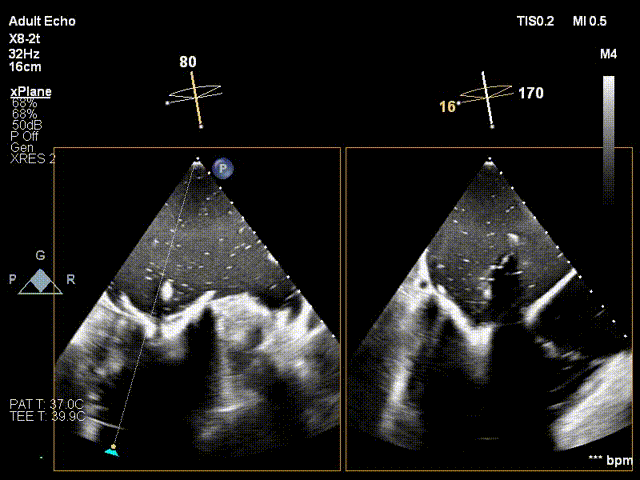

术中超声瓣膜释放

术中介入瓣膜顺利释放

术后介入二尖瓣瓣膜位置合适、瓣膜形态完整、有效瓣口面积3.7cm²,介入二尖瓣平均跨瓣压差3mmHg,无二尖瓣狭窄、无二尖瓣中心反流、无二尖瓣瓣周漏。手术顺利结束,患者术后24小时即离开监护室,回到普通病房。

术中复查造影,未见反流及瓣周漏

术后复查心超二尖瓣反流消失